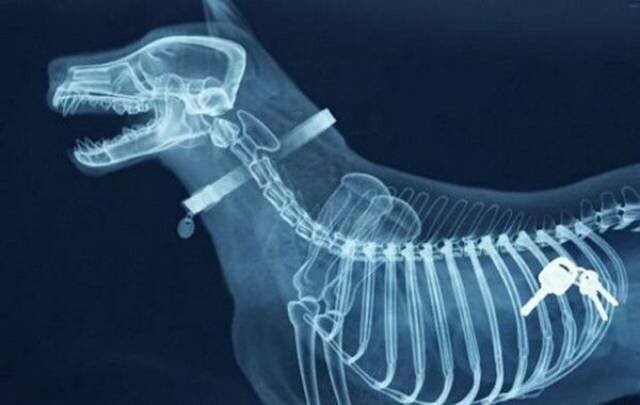

1. Ключі